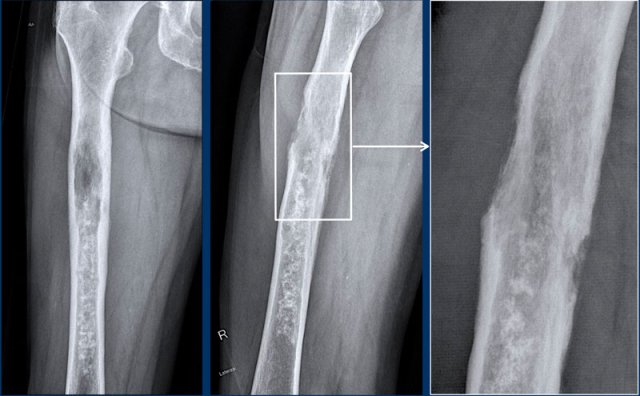

Dedifferentiated chondrosarcoma

First look at the images of a 79-year-old patient with a bone tumor.

Then continue reading.

Images

Radiographs show a large tumor in the femoral diaphysis with typical popcorn calcifications distally and a

more osteolytic component proximally.

Detailed magnified window of the

lateral view shows cortical permeation by the tumor and a high risk for a

pathological fracture.

The caudal part of the tumor appears

like an ACT with focal cortical scalloping, while the cranial part looks like a high grade CS.

Conclusion

This is the typical

presentation of a dedifferentiated chondrosarcoma, with one part behaving like a

low to intermediate grade cartilage tumor with abrupt transition to a

high-grade (sometimes non-cartilaginous) sarcomatous component.

This subtype

usually presents in older adults.

Overall survival of a dedifferentiated

chondrosarcoma is poor as compared to chondrosarcomas grade II and III, as

patients often present with pulmonary and bone metastases at the time of

diagnosis.

Continue with the next images...

Note the cortical defect on the axial

T2 DIXON and the surrounding soft tissue mass.

Part of the tumor does not enhance

and this area of mucoid indicates a high grade chondrosarcoma.

As on the radiographs, this

case is a typical dedifferentiated

chondrosarcoma, where the lower part behaves

like an ACT and the proximal part as a high grade sarcoma.

Frequently they present as a large tumor in an elderly patient.